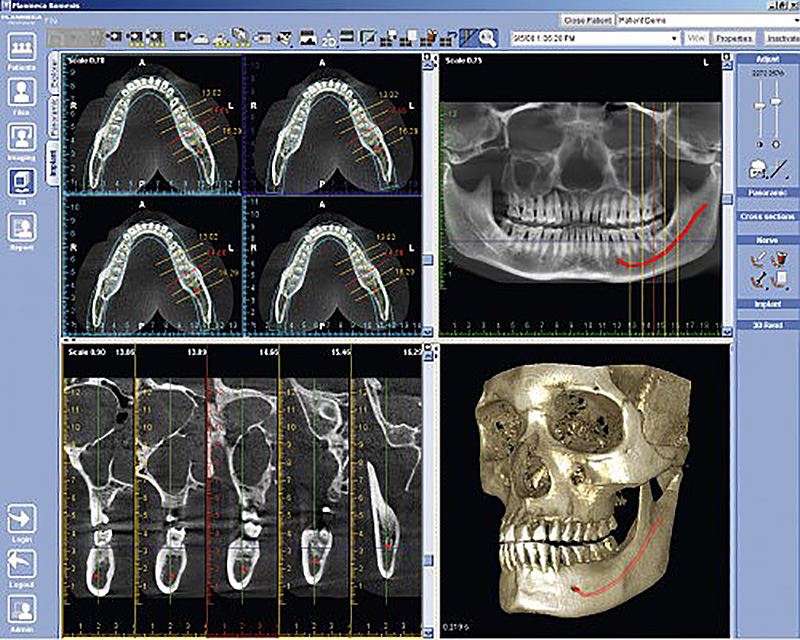

La tomografia computerizzata Dentale Cone Beam (CBCT) ha rivoluzionato la diagnostica radiologica odontoiatrica e maxillo-facciale rendendo disponibili ricostruzioni 3D delle strutture anatomiche esaminate.

La Cone Beam 3D è una tecnica radiologica di scansione tomografica utilizzata per acquisire dati e immagini di uno specifico volume del massiccio facciale o del cranio. Grazie a specifici e potenti software di elaborazione, questa tecnica offre immagini diagnostiche sui tre piani dello spazio e Volume Rendering (cioè immagini volumetriche), esponendo il paziente a dosi radianti bassissime.

L’indagine radiologica eseguita mediante acquisizione con apparecchiature CBCT dell’ultima generazione ha raggiunto un grado di accuratezza elevato che permette di integrare l’analisi 3D delle strutture anatomiche con l’esame obiettivo.

In implantologia, permette di valutare con precisione qualità e quantità di osso disponibile permettendo quindi una precisa progettazione dell’intervento chirurgico.

Inoltre grazie ad un software dedicato, si ha la possibilità di evidenziare le strutture nobili in maniera selettiva (esempio: canale mandibolare,) seguendo l’anatomia reale, e di eseguire una simulazione con la forma reale dell’impianto utilizzato scegliendone forma lunghezza e diametro più adatti.

Questo può aiutare sensibilmente il clinico nella progettazione e nell’illustrazione al paziente della soluzione adottata.